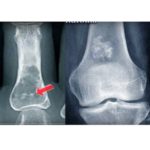

Giant Cell Tumor

Epidemiology Giant cell tumors account for approximately five percent of all primary bone tumors. Most commonly affect patients between twenty and forty years of age. There is a slight female predominance. Tumors usually present as solitary lesions. Multicentric giant cell tumors are rare, occurring in one to two percent of cases, and may be synchronous […]